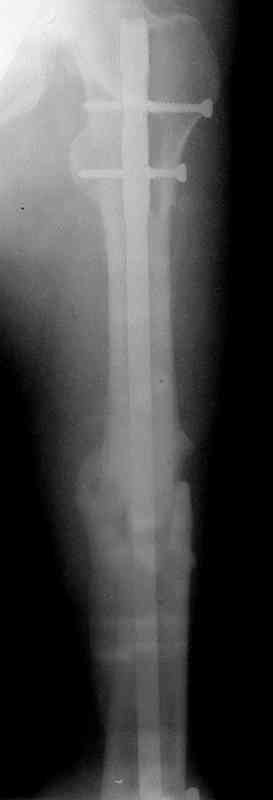

по его наружной поверхности послеоперационный рубец - рана зажила первичным натяжением. При измерении длины бедер обнаружено укорочение левого бедра на 4,5 см. На рентгенограммах этого бедра: ось конечности правильная, отмечается захождение основных костных фрагментов по длине, проксимальный конец штифта выступает слишком медиально и высоко относительно большого вертела, периостальная мозоль незначительна.22.12 - через 6 месяцев после операции, произведенной в ЦРБ, нами по поводу замедленно консолидирующего перелома левой бедренной кости с ее абсолютным укорочением под наркозом произведена операция: удаление штифта, закрытый блокирующий интрамедуллярный остеосинтез перелома левого бедра штифтом без рассверливания (UFN) длиной 40 см, диаметром 10 мм с блокированием только проксимальных отверстий (динамический остеосинтез). Наложен аппарат Илизарова на 4 полукольцах с целью удлинения укороченного бедра. Послеоперационное течение без особенностей. Ежедневно осуществляли дистракцию отломков на 1 мм. Через 3 недели после операции больной выпи-сан на амбулаторное лечение с продолжением дистракции отломков. В течение 1,5

месяцев дистракции укорочение левого бедра удалось полностью устранить. 22.02.00, т.е. через 2 месяца после повторного остеосинтеза, больному произведено дистальное блокирование штифта двумя винтами и демонтирован аппарат Илизарова. В течение 2 недель после операции больной ходил с помощью костылей, потом 2 недели с тростью. Опороспособность и функция оперированной конечности полностью восстановились через 4 недели после операции.